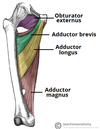

What is this muscle?

What is this muscle?